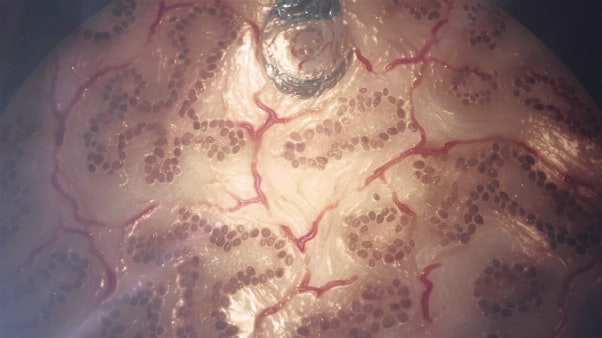

Image: Organovo's 3D printed liver tissue

Organovo's first commercial product is 3D printed liver tissue, because of its importance in pharmaceutical research. They are using it to do custom research for drug discovery, toxicity testing, metabolism studies and to monitor drug-drug interactions. It includes the three major cell types found in the liver, but not all. They can also print kidney, bone, blood vessel, and lung tissues.

The tissues live for around 40 days which is long enough to monitor biochemical interactions, genetic expressions and histology, but not even close to the lifetime needed for implants. The size is limited to 3mmx3mmx1mm, because the lack of vascular system which means the tissue must be fed from the outside. This is big enough for biopsy, but is not a whole organ. More information on the work of Organovo is included in Applications of 3D Printing 2014-2024: Forecasts, Markets, Players (www.idtechex.com/3dapps)

Top image of liver tissue: Organovo